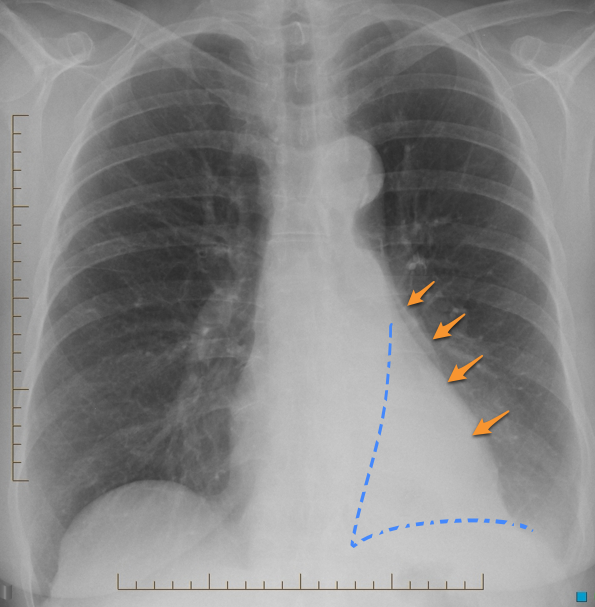

Caused by relaxation of lung adjacent to an intrathoracic lesion causing mass effect, such as a pleural effusion, pneumothorax, or pulmonary mass. Also known as compressive atelectasis. Causes: most classicaly seen adjacent to a pleural effusion. Could also be seen from adjacent compression of lung from a mass, hiatal hernia, or a large bleb - anything directly pushing on the lung.